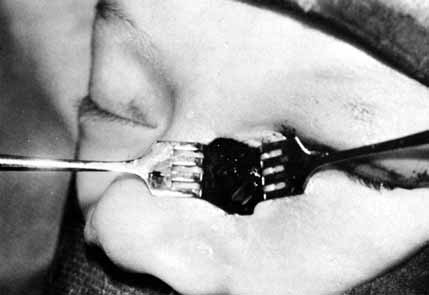

Fig. 51 Methylene blue injected through the medial canthal tendon to the area of

the assumed lacrimal sac. Fig. 51 Methylene blue injected through the medial canthal tendon to the area of

the assumed lacrimal sac.